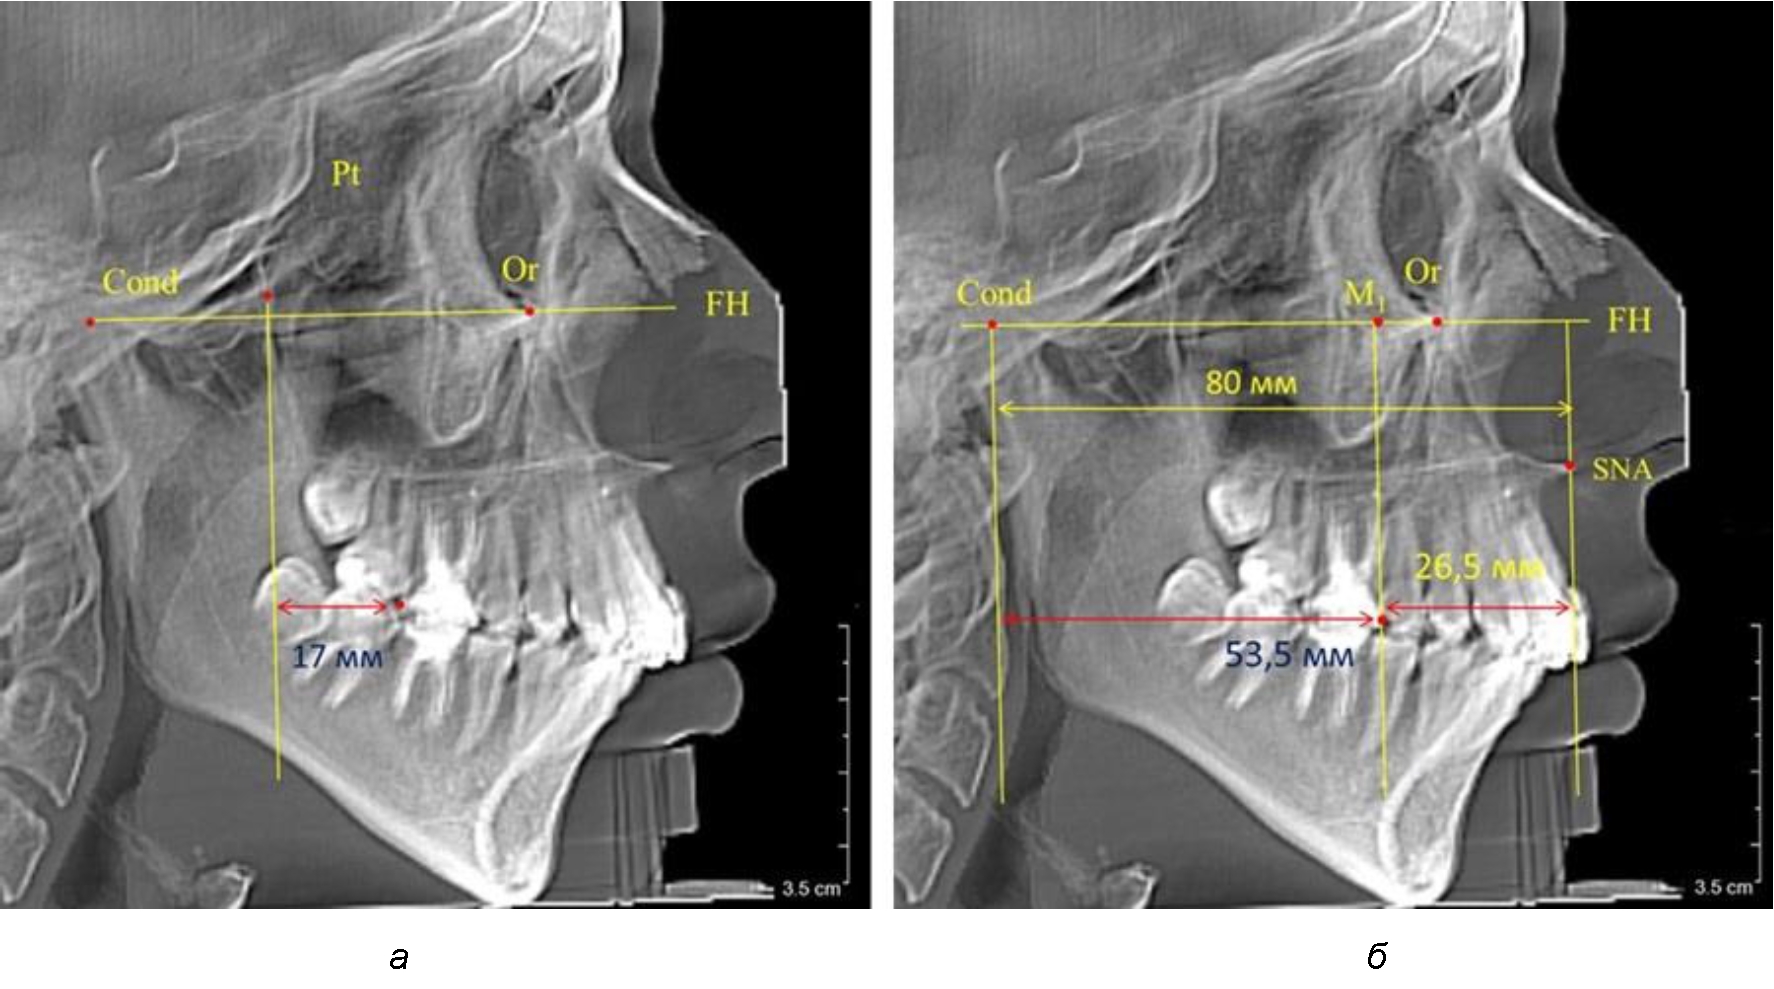

Согласно указанному методу на рентгенограммах проводили Франкфуртскую горизонталь. Учитывая мнения специалистов относительно ориентиров для построения и вариабельность положения наружного слухового прохода, в качестве задней точки использовали верхнюю выпуклость суставной головки нижней челюсти («Cond»). Передняя точка традиционно располагалась на нижнем крае глазницы и определялась как орбитальная точка Or.

Находили положение точки Pt, которая располагалась на пересечении нижнего края круглого отверстия и задней стенки крыловидно-верхнечелюстной щели, и перпендикулярно к Франкфуртской горизонтали проводили крыловидную вертикальную линию, которую принято обозначать как плоскость PTV. Расстояние от крыловидной вертикальной плоскости PTV до дистальной поверхности верхнего первого постоянного моляра определяло его положение, которое, по мнению R. E. McDonald, соответствовало возрасту пациента, увеличенному на 3 мм.

При проведении анализа к Франкфуртской горизонтали проводили передний и задний перпендикуляры. Передний спинальный перпендикуляр проходил через выступающую точку передней носовой ости (spina nasalis anterior – SNA), а задний суставной перпендикуляр опускали из кондилярной точки Cond. Молярный перпендикуляр проводили через медиальную поверхность первого постоянного моляра. Указанная вертикаль отделяла замещающие зубы постоянного прикуса от добавочных зубов (постоянных моляров), что вполне логично для анализа положения первых постоянных моляров в гнатическом комплексе (рис. 1).

Рис. 1. Метод определения положения первых верхних моляров по Ralph E. McDonald (а) и по предложенному методу (б)